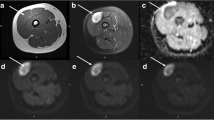

Already widely used in neuroradiology, magnetic resonance spectroscopy (MRS) has recently gained also a role in the musculoskeletal field. One of the main applications is the assessment of malignancy in musculoskeletal tumors since specific metabolites (trimethylamine/choline-containing compounds including phosphocholine, glycerophosphocholine, and free choline) are distinctively increased in malignant lesions, and they are considered as a marker of malignancy [45]. To date, the literature results in musculoskeletal MRS investigated the qualitative analysis of the choline or trimethylamine peak as a marker for malignancy [21, 44]. Doganay et al. [4] obtained a sensitivity of 72.2%, specificity of 83.3%, and an accuracy of 76.6% in detecting malignant bone and soft tissue tumors. In another group [5], sensitivity and specificity were 95% and 83%, respectively. They concluded that the absence of choline peak is highly predictive of benign tumors and that 1H-MRS is a feasible approach to differentiate malignant from benign tumors (Fig. 3). In a series of Russo et al., all tumors with a mitotic index greater than 2/10 HPF had a positive choline peak and were malignant and correlation between 1H-MRS findings and mitotic index was high [16]. However, some benign tumors show a positive choline peak, and also a large number of inflammatory lesions may produce a high choline peak [16].

MRI axial images of a solid lesion at the level of the flexor tendons of the wrist showing a low signal intensity on T1- and T2-weighted sequences (a, b) and intense contrast enhancement after gadolinium injection (c). The MR spectroscopy analysis after ROI positioning shows a choline peak (d). The imaging features are consistent with a giant cell tumor of the tendon sheaths (GCTTS)